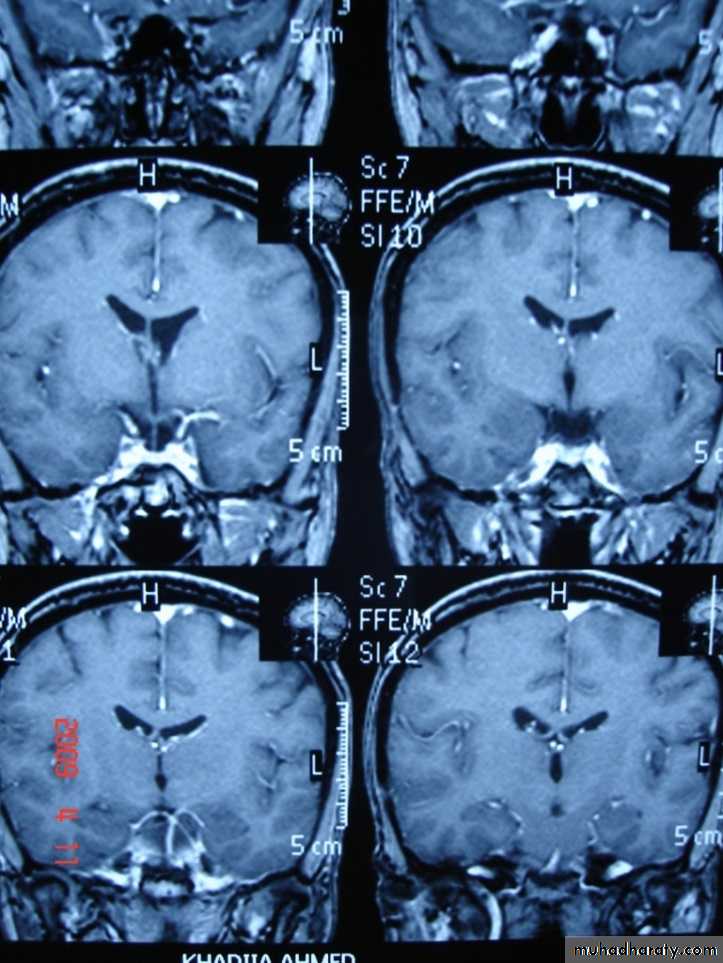

CORONAL SECTION OF BRAIN ( T1w post contrast injection)CONGENITAL LESION OF BRAIN

Congenital lesion of brain are well seen by MRI & CT scan but MRI has the advantage of absence of ionizing radiation so can be used safely in children.Congenital hydrocephalus:

Congenital hydrocephalus: Congenital hydrocephalus in infant & young children can be classified as communicating & non – communicating.Communicating Congenital hydrocephalus :

1-free communication between ventricles & basal cisterns.

2- obstruction to flow of csf is in the subarachnoid space or basal cisterns.

3- this is due to meningeal irritation by hemorrhage ,infection or trauma .

4- all ventricles are enlarged & basal cisterns may be prominent.

NON- Communicating Congenital hydrocephalus :

CSF flow is obstructed within the ventricular system , usually at 3rd ventricle , aqueduct or 4th ventricular level.The ventricles are dilated above the level of obstruction.

AQUIDUCT STENOSIS:

AQUIDUCT STENOSIS: It is the most common cause of NON- Communicating Congenital hydrocephalus , it is congenital obstruction or stenosis of the aqueduct which result in hydrocephalus involving the 3rd & lateral ventricles.ARNOLD CHIARI MALFORMATION